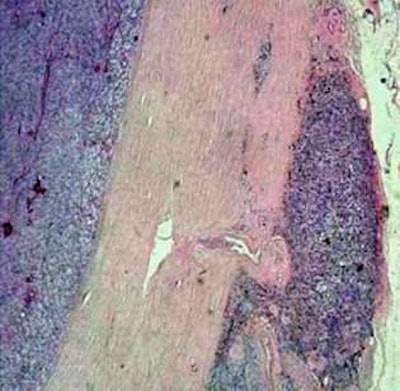

Corresponding histological specimen (HE stain, enlargement 40x), correlating well with MR microscopy."MR microscopy visualizes the eye and its surrounding lipid tissue. This permits us to ascertain whether a tumor is growing into the surrounding tissue or not, which can play a decisive role in designing a therapy," he noted at the meeting. "Histological interpretation of the tumors produced, for all cases, identical results as in MR microscopy. For example, pathologists established that two tumors had grown into the surrounding tissue, congruent with our previous diagnosis based on MR microscopy."